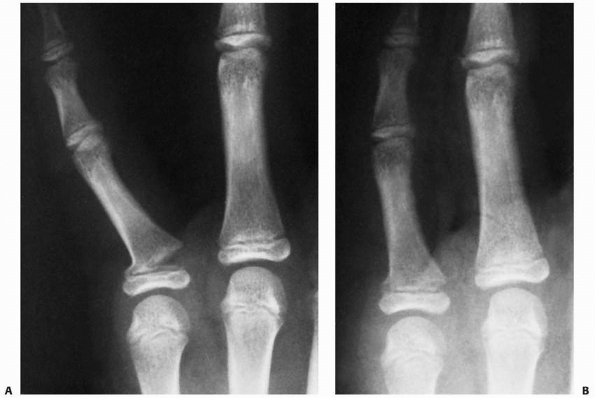

![]() |

FIGURE 8-32 A. A 10-year-old girl with a displaced unicondylar fracture of the ring finger proximal phalanx. B. Clinical examination reveals malrotation of the digit. C. Dorsal exposure with incision between lateral band and central slip. D. Exposure of displaced fracture fragment. (continues)

FIGURE 8-32 (continued) E. Fracture reduced with Kirschner-wire fixation. F.